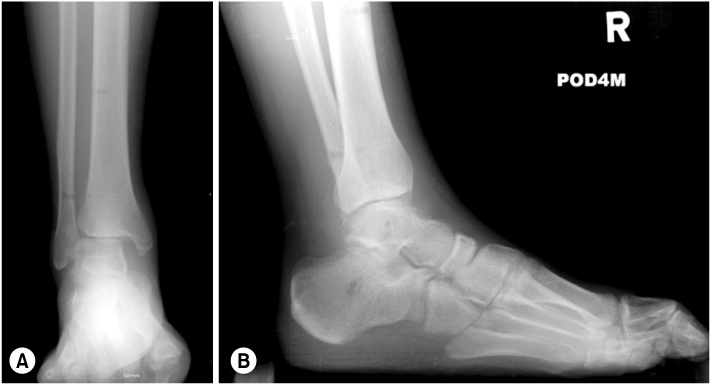

Fig. 2

(A) Anteroposterior view of right ankle shows widening of tibiofibular space and medial clear space.

(B) Lateral view shows equinus and flexion deformity of great toe.

Fig. 2 (A) Anteroposterior view of right ankle shows widening of tibiofibular space and medial clear space. (B) Lateral view shows equinus and flexion deformity of great toe.